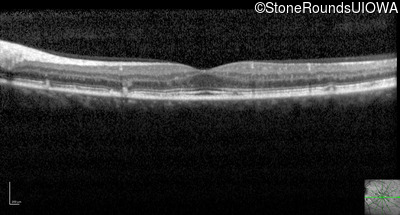

Optical Coherence Tomography - Right - 20/20 -2

Exemplar / OCT Stack

OCT Stack